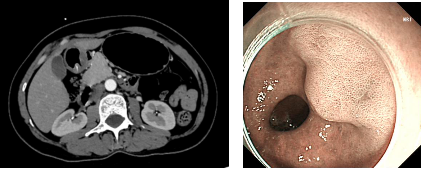

为精准锁定病因,医疗团队为患者完善腹部 CT、胃镜、超声内镜等联合检查,最终确诊为胃窦肌层包埋性异物。该异物长期刺激胃壁,造成黏膜持续微小破损、慢性隐匿失血,最终导致重度贫血,此类病例在临床较为罕见。

超声内镜清晰显示:胃窦壁内低回声管状肌性组织